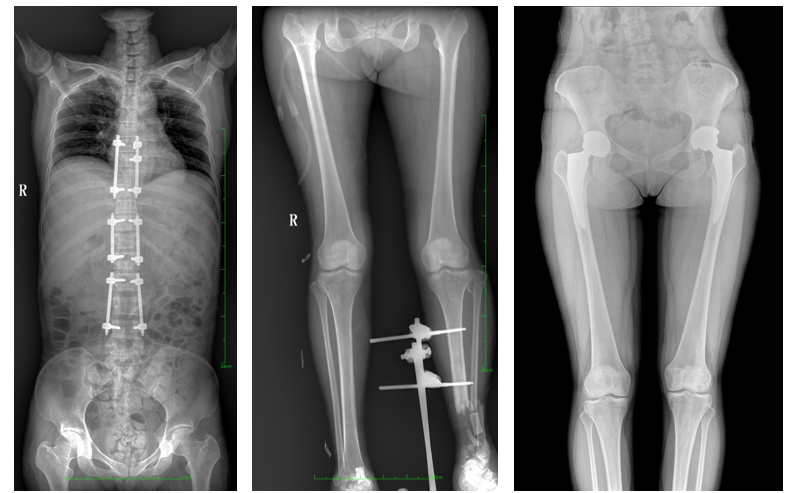

普愛醫療自主研發的一款數字化X光機——PLX8600大視野平板動態DR,擁有43cm*86cm超大有效視野,可一次性拍攝全脊柱、雙下肢的影像視野。使全脊柱及雙下肢能夠得到完整清晰的成像,為臨床在脊柱側彎畸形和下肢骨關節病變診斷、治療方案制定及治療后復查提供精準的測量。

數字化X光機影像